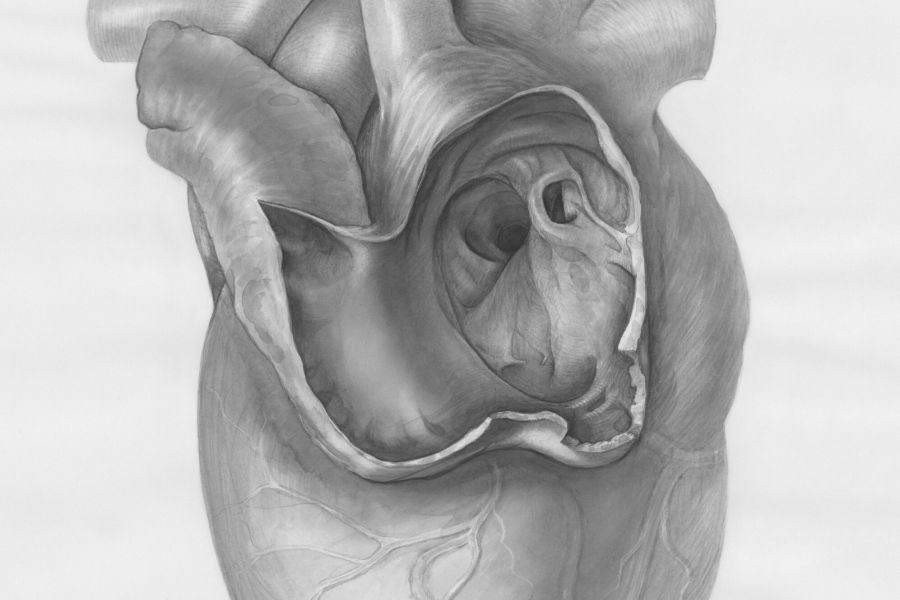

Informatiemarkt over hartfalen in Franciscus

Tijdens de Nationale Hartfalenweek vraagt Franciscus aandacht voor hartfalen, een aandoening die ongeveer een half miljoen Nederlanders treft. Om patiënten en geïnteresseerden te informeren en ondersteunen, organiseert Franciscus op dinsdag 21 april een gratis informatiemarkt in de Centrale Hal van Franciscus Gasthuis in Rotterdam. Bij hartfalen pompt het hart minder goed bloed rond, wat grote […]